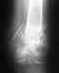

Межвертельный перелом бедра со смещением у женщины-диабетика, 52-х лет. Без операции и гипса. Прошло 4 месяца.

Два месяца провела в стационаре на вытяжении.Операцию не стали делать из-за возможных осложнений на фоне диабета.Гипс не стали накладывать по той же причине.Выписали домой со смещением 2 см и только начавшей образовываться мозолью. Рекомендации травматолога -месяц постельного режима с отведением ноги в сторону. Пролежала два месяца, отведение ноги особо не соблюдалось. За 4 месяца мышцы атрофировались. Купили ходунки. С трудом встаёт, передвигаться нет сил пока. Кости в переломе ещё подвижны, чувствуется, что сращения нет пока. Подскажите, что нам делать? К кому обратиться за консультацией и помощью. Транспортировать её нет никакой возможности.

Дома мало что можно сделать. Надо в любом случае добираться до больницы, делать снимки, и тогда решать, что делать. Если несращение - конечно надо делать операцию. Какую именно - снимок надо увидеть.